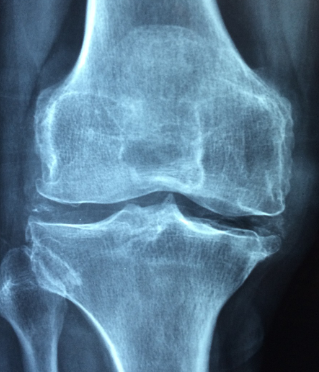

콘드로이친은 우리 몸의 관절 부위에서 발견되는 연결 조직입니다. 이 중요한 조직은 뼈와 뼈 사이에 위치하여 충격을 흡수하고 관절을 보호하는 역할을 합니다. 콘드로이친은 무척 부드럽고 유연하며, 미끄러운 표면을 가지고 있어 관절 움직임을 원활하게 합니다.

1. 충격 흡수: 콘드로이친은 관절에 가해지는 충격이나 압력을 흡수하여 관절 부위를 보호합니다. 이로써 뼈에 가해지는 압력을 완화시켜 관절염과 같은 질환의 발생을 예방할 수 있습니다.

2. 마찰 감소: 콘드로이친은 관절의 움직임을 원활하게 하기 위해 마찰을 감소시킵니다. 이는 관절 부위의 미끄러운 표면과 윤활제 역할을 수행하여 관절 운동을 원활하게 합니다.

4. 관절 보호: 콘드로이친은 관절을 보호하고 안정성을 유지하는 역할을 합니다. 관절 부위에서 자극을 받을 경우 콘드로이친은 이를 흡수하여 관절의 손상을 최소화하고 보호합니다.

콘드로이친 결핍증은 콘드로이친이라는 단백질의 결핍으로 인해 발생하는 질환입니다. 콘드로이친은 연골 조직에서 중요한 구성 요소로 작용하며, 관절의 움직임과 충격 흡수에 기여합니다. 따라서 콘드로이친 결핍증은 연골의 손상 및 염증으로 인해 관절 통증, 관절 강직, 관절의 기능 저하 등의 증상을 유발할 수 있습니다.